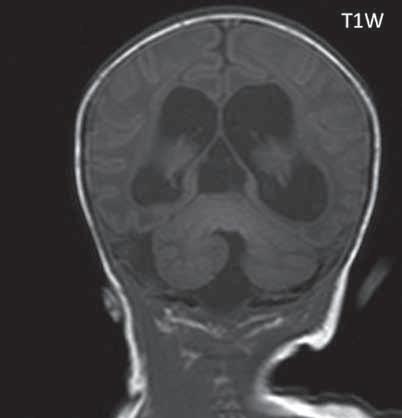

I.1.8 Dandy-Walkerova malformace (D-W variant, D-W komplex, D-W spektrum )

V současné odborné literatuře je nejčastěji užíván termín D-W spektrum, který snad nejlépe vyjadřuje velmi široké možnosti vrozených změn zadní jámy lební. Mezi tuto skupinu cystických malformací zadní jámy lební pak řadíme klasickou malformaci D-W a její varianty, mega cisterna magna, arachnoidální cystu zadní jámy lební a retrocerebelární vak (Blake’s pouch cysta). Zařazení malformace do určité klinické jednotky není někdy jednoznačné, proto je možná výhodnější a přesnější vycházet z přesného popisu zobrazených změn. Příčina D-W malformace není známa, nabízejí se dvě hypotézy: 1. nepropustná spodina IV. komory, eventuálně uzávěr nebo pozdní otevření otvorů, kterými proudí likvor ze IV. komory. 2. primární hypogeneze mozečku. Embryonální vývoj mozečku ze všech hlavních struktur mozku trvá nejdelší dobu, a proto je velmi vulnerabilní k různým patologickým příčinám po dlouhou dobu svého vývoje.

Zobrazení

D-W malformace je charakterizována hypoplazií vermis mozečku, rozšířením IV. mozkové komory, která se často cysticky vyklenuje dorzálně a může imitovat arachnoidální cystu, rozšířením zadní jámy lební a vysokým úponem tentoria s confluens sinum nad lambdovým švem. Okcipitální kost může být vlivem tlakových změn remodelována, existují i případy s porušením její kontinuity a encefalokélou. Hydrocefalus pozorujeme v 80 %, častá je přítomnost dysgeneze corpus callosum, schizencefalie.

D-W variant byl vyčleněn pro případy, kdy všechny základní příznaky nemusí být plně vyjádřeny nebo může některý zcela chybět. Bývá přítomna hypoplazie mozečku, což je dominantní příznak, IV. komora je obvykle rozšířena, někdy pozorujeme, že tvarem připomíná na axiální řezu „klíčovou dírku“, zadní jáma lební naopak rozšířena nebývá.

Mega cisterna magna je struktura likvorového signálu, lokalizována dorzálně a kaudálně od mozečku, není doprovázena hypoplazií mozečku, rozšířením IV. komory ani hydrocefalem, někdy může být tlakem zeslabená lamina interna lebky v zadní jámě lební. Diferenciální diagnostika mezi mega cisterna magna a arachnoidální cystou je mnohdy obtížná a může nám pomoci CT cisternografie (chybí nebo pozdní pronikání kontrastní látky do arachnoidální cisterny), určité informace může přinést MR vyšetření pulzace likvoru.

Retrocerebelární vak (Blake’s pouch cysta) vzniká embryonálně vyklenutím části stropu IV. komory (velum

mediale superius) do cisterny magna (vak je vyplněn likvorem, chybí foramen Magendii). Je charakterizován rozšířenou a široce otevřenou IV. komorou, která komprimuje bazální cisterny, hypoplazie vermis mozečku naopak není přítomna. Široce komunikující IV. komora (někdy obsahuje choroidální plexus), přičemž komunikace mezi komorovým systémem a subarachnoidálními prostory je pouze přes laterální foramina Luschkae.

Obr. I.1.8a Dandy-Walkerova malformace, rozšířená IV komora (tvar klíčové dírky)

Obr. I.1.8b Dandy-Walkerova malformace, rozšířená IV komora široce komunikující s cisterna magna, hypotrofie mozečku (snímky zapůjčeny z archivu prim doc MUDr M Mechla, Ph D, MBA)

Obr. I.1.8c Dandy-Walkerova malformace, rozšířená IV komora široce komunikující s cisterna magna, hypotrofie mozečku (snímky zapůjčeny z archivu prim doc MUDr M Mechla, Ph D, MBA); stejný pacient jako na obr I 1 8b

Obr. I.1.8d Dandy-Walkerova malformace, rozšířená IV komora široce komunikující s cisterna magna, hypotrofie mozečku, vysoký úpon tentoria (šipka) (snímky zapůjčeny z archivu prim doc MUDr M Mechla, Ph D, MBA); stejný pacient jako na obr I 1 8b, c

Obr. I.1.8e Dandy-Walkerovo spektrum (hypoplazie vermis, IV komora je rozšířená a široce zeje) (snímky zapůjčeny z archivu as MUDr J Lisého, CSc )

Obr. I.1.8f Dandy-Walkerovo spektrum (hypoplazie vermis, IV komora je rozšířená a široce zeje) (snímky zapůjčeny z archivu as MUDr J Lisého, CSc ); stejný pacient jako na obr I 1 8e

Obr. I.1.8g Dandy-Walkerovo spektrum (hypoplazie vermis, IV komora je rozšířená a široce zeje), (snímky zapůjčeny z archivu as MUDr J Lisého, CSc ); stejný pacient jako na obr I 1 8e, f

Obr. I.1.8h Mega cisterna magna

Obr. I.1.8ch Retrocerebelární vak (Blake’s pouch cyst), široce komunikující IV komora, chybí foramen Magendii